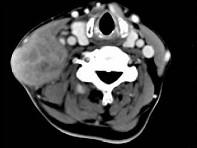

问题 65岁男性,吸烟史30余年,近半年来颈部出现疼痛性肿块,CT扫描如图所示,请选择最可能诊断 ( )

选项 A、淋巴结转移癌 B、软组织脓肿 C、血管瘤 D、神经鞘瘤 E、淋巴结核

答案 A